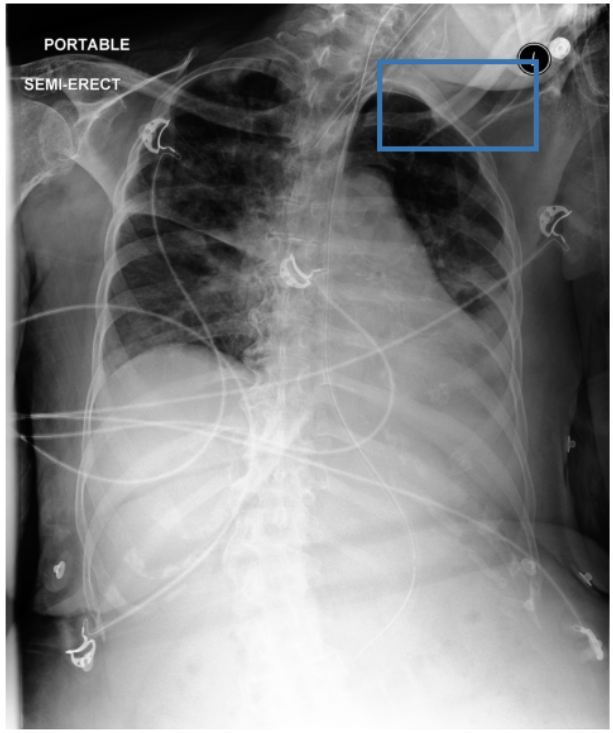

To address these drawbacks, state-of-the-art models such as MAIRA-2 [3] explicitly incorporate grounded report generation to better align local visual evidence with the textual findings. For example, MAIRA-2 is trained on a diverse set of localization-based tasks, including phrase grounding and grounded report generation. However, as shown in Figure 1, current models often exhibit a bias in which the target visual regions become overly associated with abnormal findings, leading to false positives in medical reports.

As shown in Table 1, our data composition reflects this imbalance: over 12.9M instances from Chest ImaGenome dominate the much smaller MS-CXR (815 PG instances) and PadChest-GR (12k instances) datasets. Beyond the imbalance between datasets, each dataset also exhibits substantial intra-dataset class imbalance. For example, anatomical regions in AGRG and semantic categories in PG are unevenly represented, leading the model to overfit frequent regions, neglect rare but clinically important ones, and hallucinate findings (Figure 1). Our curriculum framework addresses both sources of imbalance.

While MAIRA-2 exhibits a slightly lower hallucination rate for a few anatomies (e.g., ‘Cardiac Silhouette’), CURE consistently achieves a significantly lower contradiction rate and higher entailment rate across almost all categories. This improved performance likely stems from a key difference in the training data composition. Standard phrase grounding, used by MAIRA-2, is inherently biased towards abnormal findings. In contrast, our AGRG formulation exposes the model to both normal and abnormal descriptions for each anatomical region, leading to a more balanced and reliable generative process that mitigates the tendency to hallucinate abnormalities.